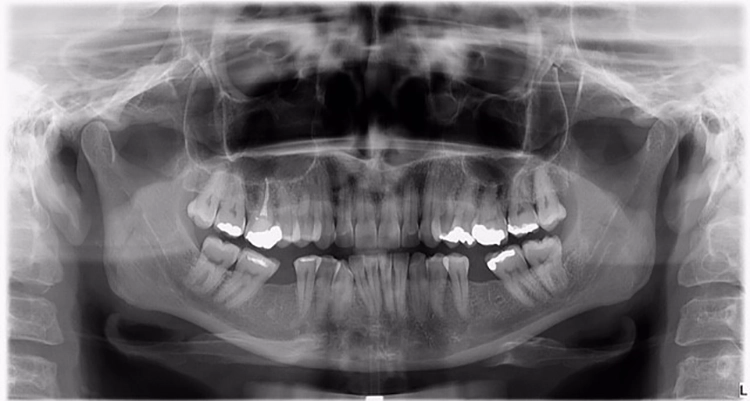

Abb. 2: Repräsentativer Fall von ABH Grad B Septus Typ II. a) Ansichten vor der Installation. Röntgenaufnahme der periapikalen Läsion an einem wurzelkanalbehandelten Molaren und klinische Ansicht der Typ-II-Socket nach der Extraktion. b) Die Ansichten nach der Installation zeigen das Implantat innerhalb des interradikulären Septums und das über dem Implantat platzierte A-PRF. c) Nachuntersuchungen nach 10 Tagen bzw. 2,1 Monaten. Die Röntgenaufnahme zeigt die Knochenbildung zwischen der Sinusmembran und dem apikalen Teil des Implantats. d) Jüngste Nachuntersuchung nach Einsetzen der Prothese.

Abb. 3: Repräsentativer Fall von Grad A Typ I. a) Präoperative Ansicht. Röntgenbild der periapikalen Läsion an einem wurzelkanalbehandelten Molaren. Die Höhe des Alveolarknochens zeigt Grad A an. b) Klinische und radiographische Ansicht der Implantatinsertion unter Verwendung einer Einheilscheibe mit großem Durchmesser (6×8 mm). A-PRF wurde um das Implantat und unter der Scheibe platziert. c) Nachuntersuchung nach 5,9 Monaten vor und nach der Zementierung und Aufbereitung. d) Jüngste Nachuntersuchung nach Einsetzen der Prothese

Abb. 4: Repräsentativer Fall von Grad A Typ III. a) Ansichten vor der Implantation. Röntgenbild der periapikalen Läsion an einem wurzelkanalbehandelten Molaren. b) Die Extraktionsalveole zeigt ein interradikuläres Septum vom Typ III (B).